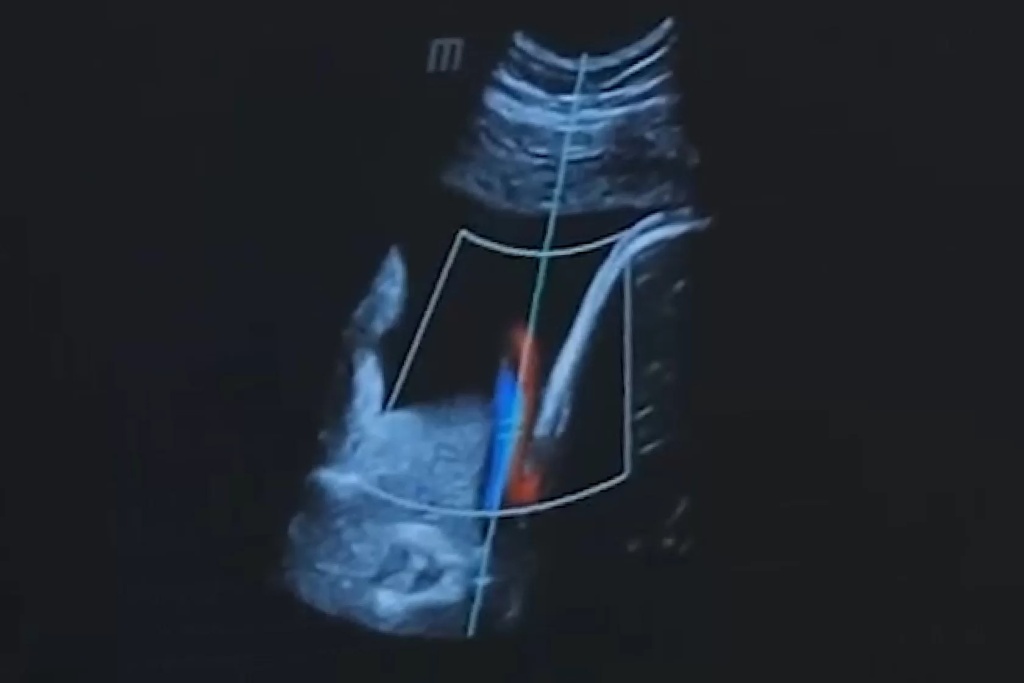

Ультразвуковое исследование — это один из самых широко используемых методов диагностики в современной медицине. Оно позволяет визуализировать внутренние органы и ткани с высокой точностью и детализацией. Однако в некоторых случаях качество изображения может быть недостаточно хорошим, например, при обследовании пациентов с избыточной массой тела или с плотными тканями.

Для улучшения качества УЗИ изображений был разработан режим тканевой гармоники. Эта технология основана на выделении гармонической составляющей ультразвуковых колебаний, которые возникают в тканях при прохождении через них ультразвукового сигнала.

Режим тканевой гармоники в медицинской диагностике базируется на использовании высокочастотных звуковых волн, которые позволяют лучше проникнуть в ткани организма. Этот метод улучшает разрешение изображения и способен выделять структурные особенности тканей, что особенно важно при обследовании органов с различной плотностью.

Принцип работы режима тканевой гармоники можно объяснить следующим образом. Ультразвуковой сигнал, посылаемый датчиком УЗИ-аппарата, имеет определенную частоту. При прохождении через ткани этот сигнал вызывает колебания этих тканей. Колебания тканей также имеют определенную частоту, но она в два раза выше частоты исходного сигнала.

Гармоническая составляющая ультразвуковых колебаний — это та часть колебаний, частота которой в два раза выше частоты исходного сигнала. Режим тканевой гармоники позволяет выделить эту составляющую из отраженного от тканей сигнала.